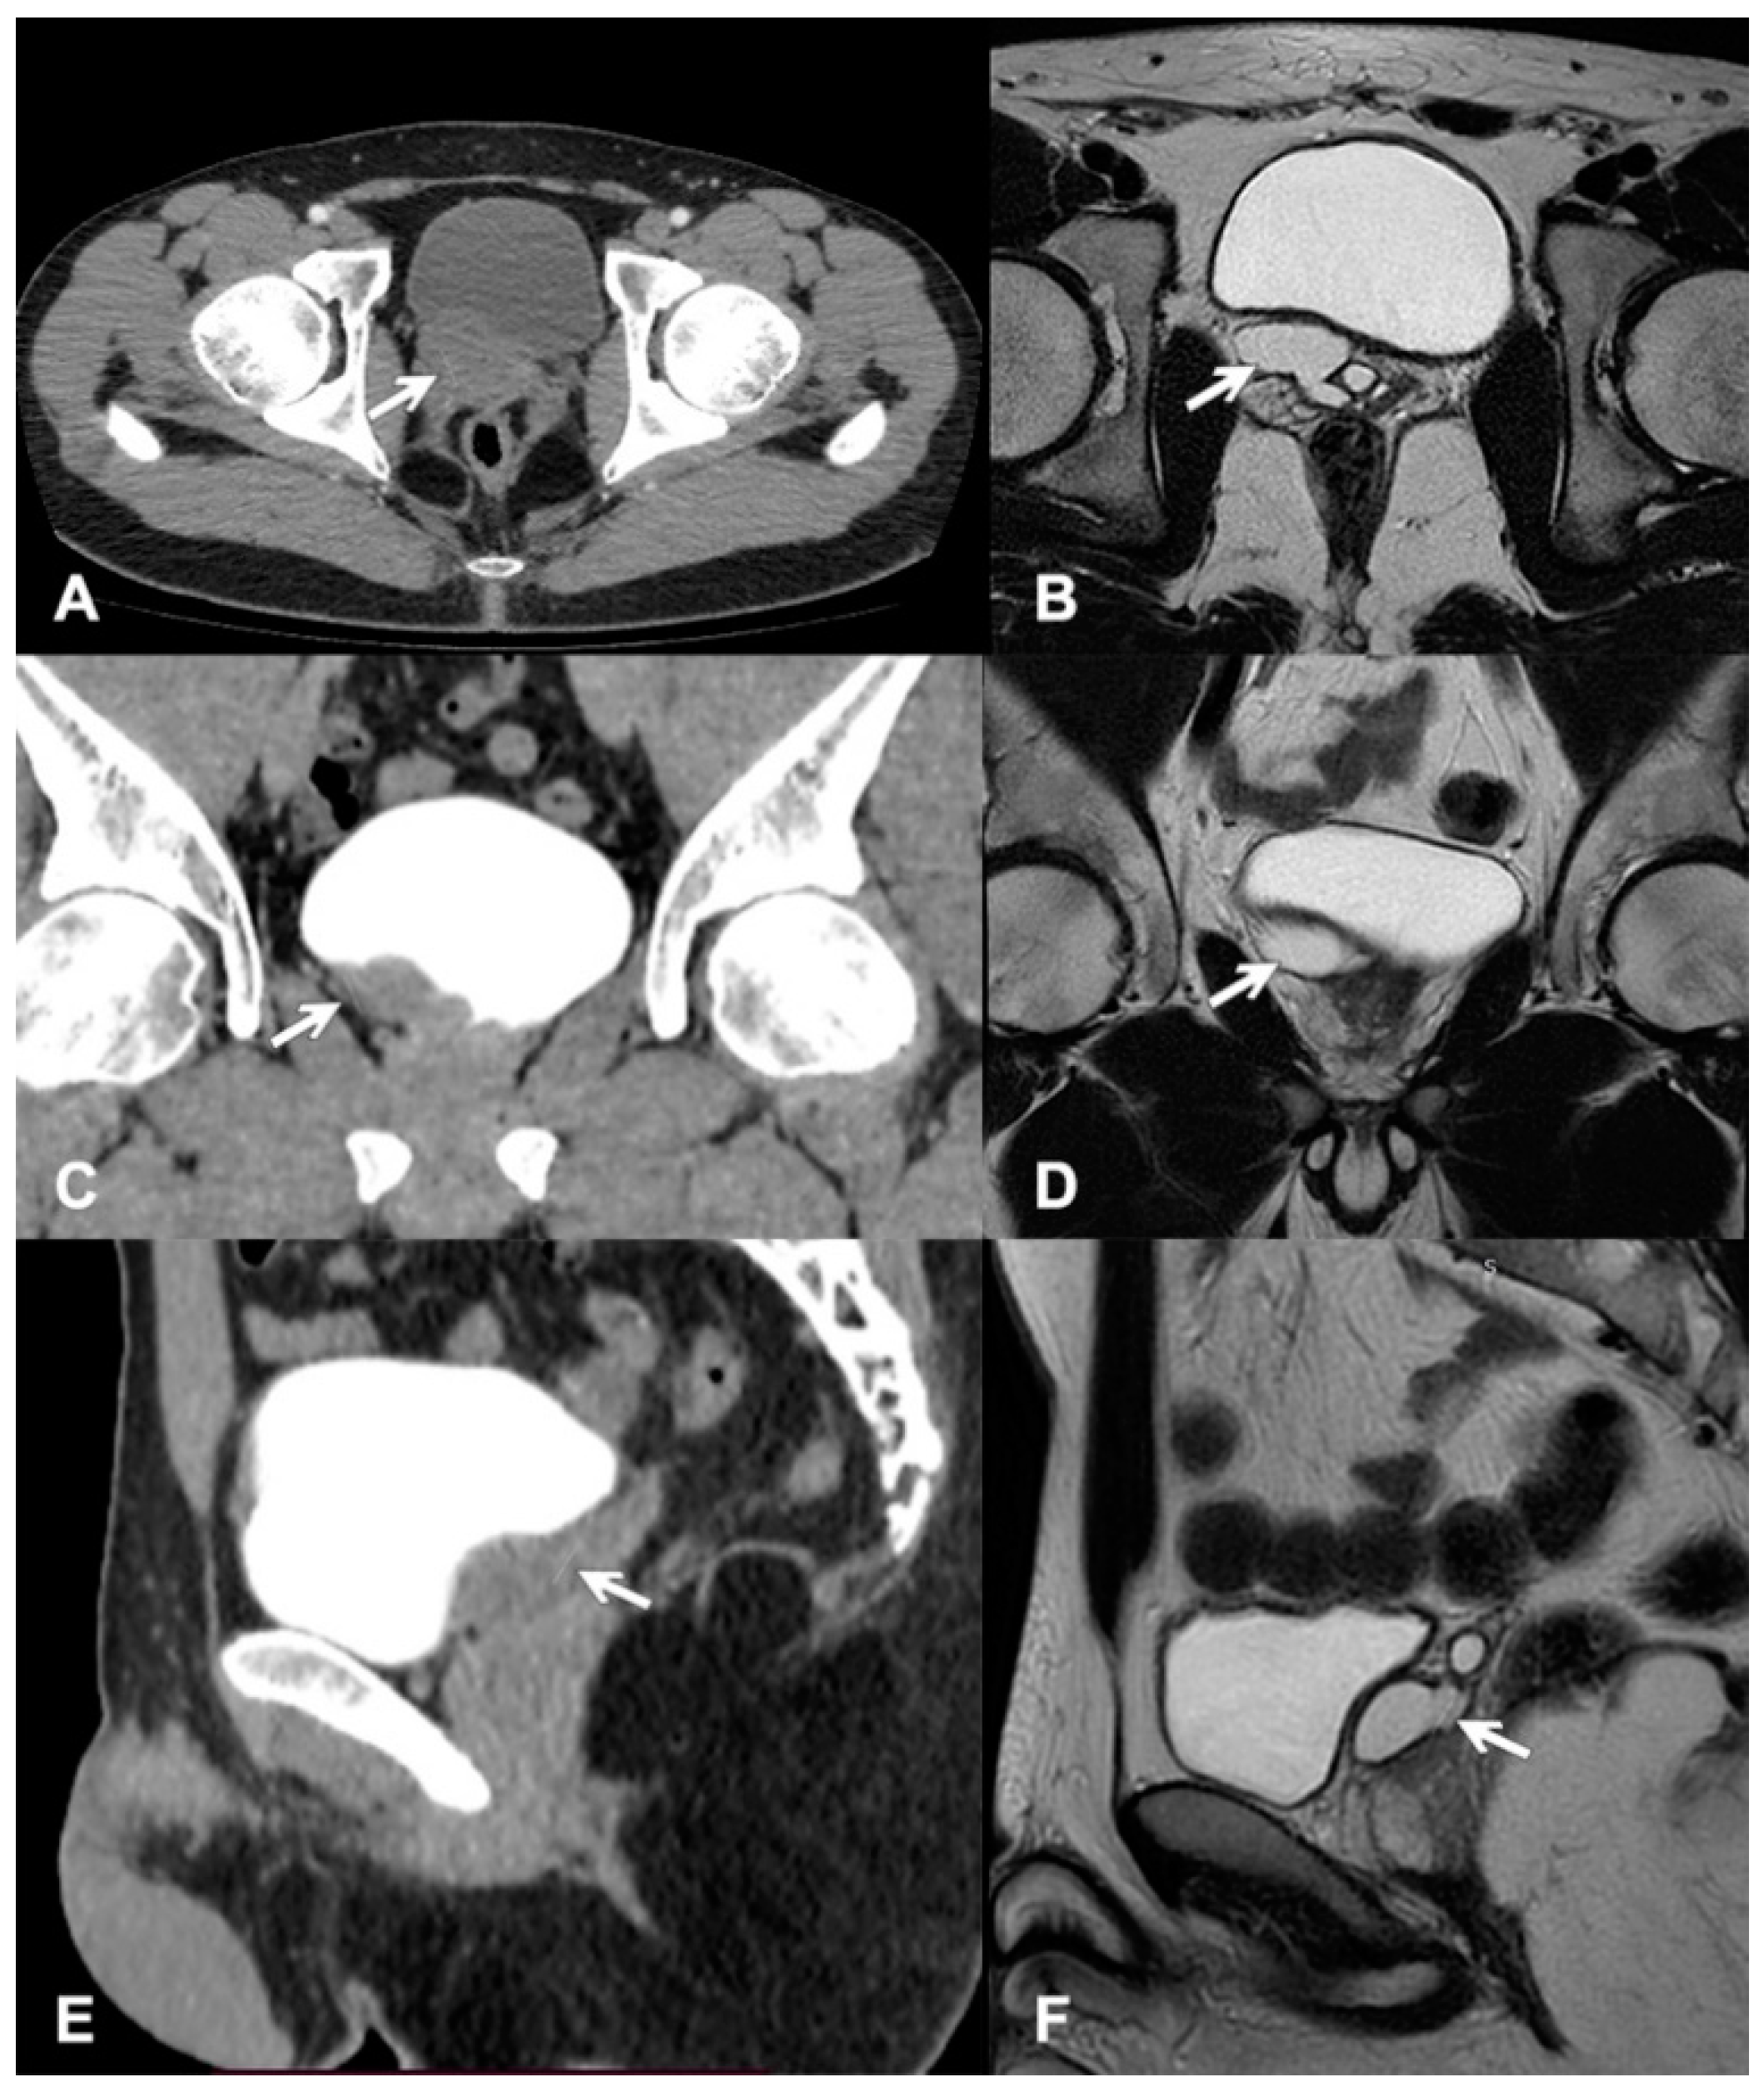

Zinner Syndrome—A Rare Cause of Recurrent Epididymitis and Infertility

2. Case Report